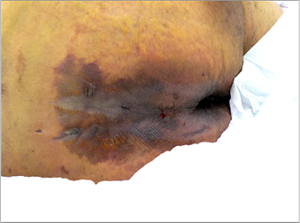

がんの進行により全身状態は変化していくが、褥瘡と関係するのは主にがん悪液質、低栄養、るい痩、浮腫、がん性疼痛、末梢神経障害などである。がんの進行に伴い、これらの状況も進み褥瘡発生のリスクが高まる。がんの場合、がん性疼痛のコントロールのために究極の選択として褥瘡の悪化や予防対策(疼痛を伴う体位変換)を諦め、疼痛対策を優先しなければならない場合もあり15)そのような時は特に発生しやすくなる(図3)。

図3 がん終末期(肝細胞がん)仙骨部周囲に発生

予防管理の継続中に写真の状態を発見し、2日後に死亡される。

(写真提供:西林直子氏(奈良県立医科大学附属病院))